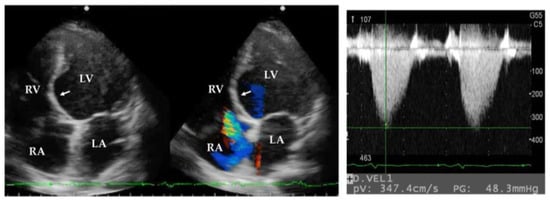

TTE is a non-invasive method to screen for PH from all causes. TTE is particularly suitable for patients with sarcoidosis because cardiac evaluation can be performed at the same time [44,45]. An estimated PAP can be assessed by regurgitant tricuspid jet on TTE (Figure 2), but tricuspid regurgitant is not detected in all patients. Additionally, the accuracy of the estimated PAP is reduced in patients with fibrotic lung disease. Therefore, TTE should not be used as a definitive PH diagnostic tool. RHC is the gold standard method for the diagnosis of PH. In a cross-sectional study of patients with idiopathic pulmonary fibrosis using TTE and RHC data, TTE could accurately estimate mean PAP in approximately 40% of patients [46].

Figure 2.

Transthoracic echocardiographic images of a patient with SAPH. Transthoracic echocardiography demonstrates a septal thinning (arrow) and regurgitant tricuspid jet, suggesting pulmonary hypertension in a patient with cardiac sarcoidosis. SAPH, sarcoidosis-associated pulmonary hypertension; RA, right atrium; RV, right ventricle; LA, left atrium; LV, left ventricle.